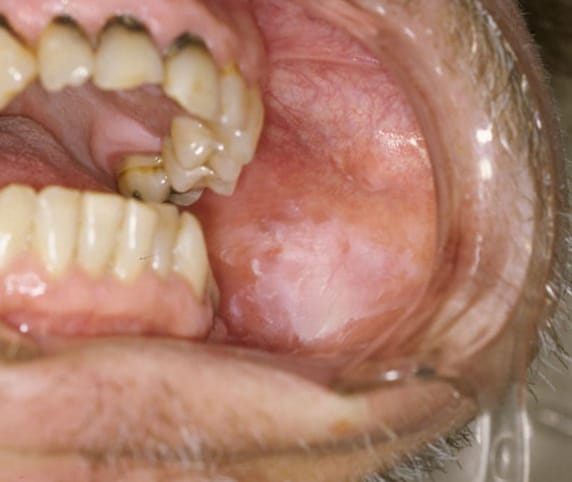

Differing from their homogeneous counterparts, nonhomogeneous leukoplakia lesions are not white in their entirety (see image 2). These lesions also display areas of erythroplakia and can include spots that appear erosive, ulcerated, nodular, as well as display another subset of oral leukoplakia, proliferative verrucous leukoplakia (PVL).1,4,5